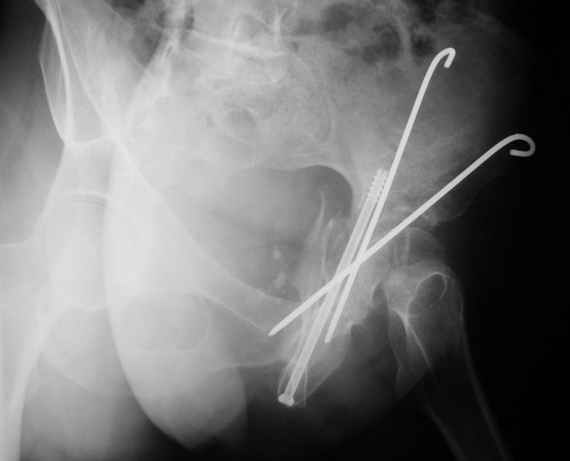

10.02.04

12.04.04

02.06.04

Высылаю пример еще одного случая, остеосинтез пластиной из подвздошного доступа.